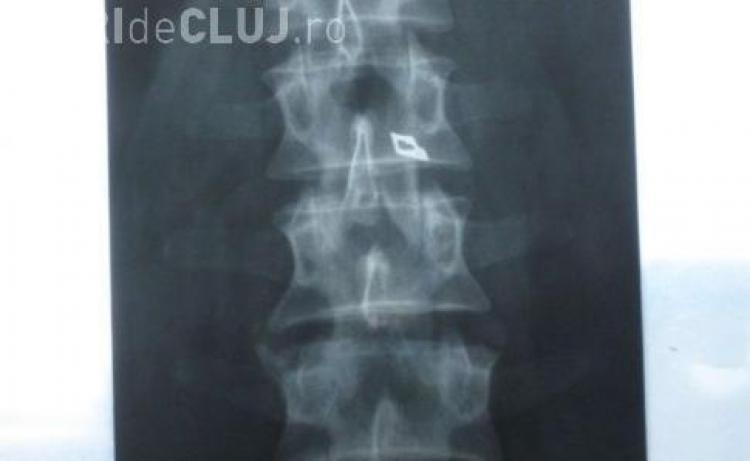

Oradeanul a fost operat in 2004 la Clinica de Neurochirurgie din Cluj, de o echipa de medici condusa de chirurgul Stefan Florian. Barbatul a fost externat si dupa circa un an a inceput sa se simta rau. "Am inceput sa ma simt rau si aveam o umflatura si o roseata la spate in zona in care a fost operatia. Am facut o radiografie si mi s-a vazut acolo un varf de bisturiu. Am plecat la Bucuresti, unde am fost operat si mi s-a scos varful de bisturiu de langa coloana vertebrala", a povestit Nistor pe scurt drama prin care a trecut.